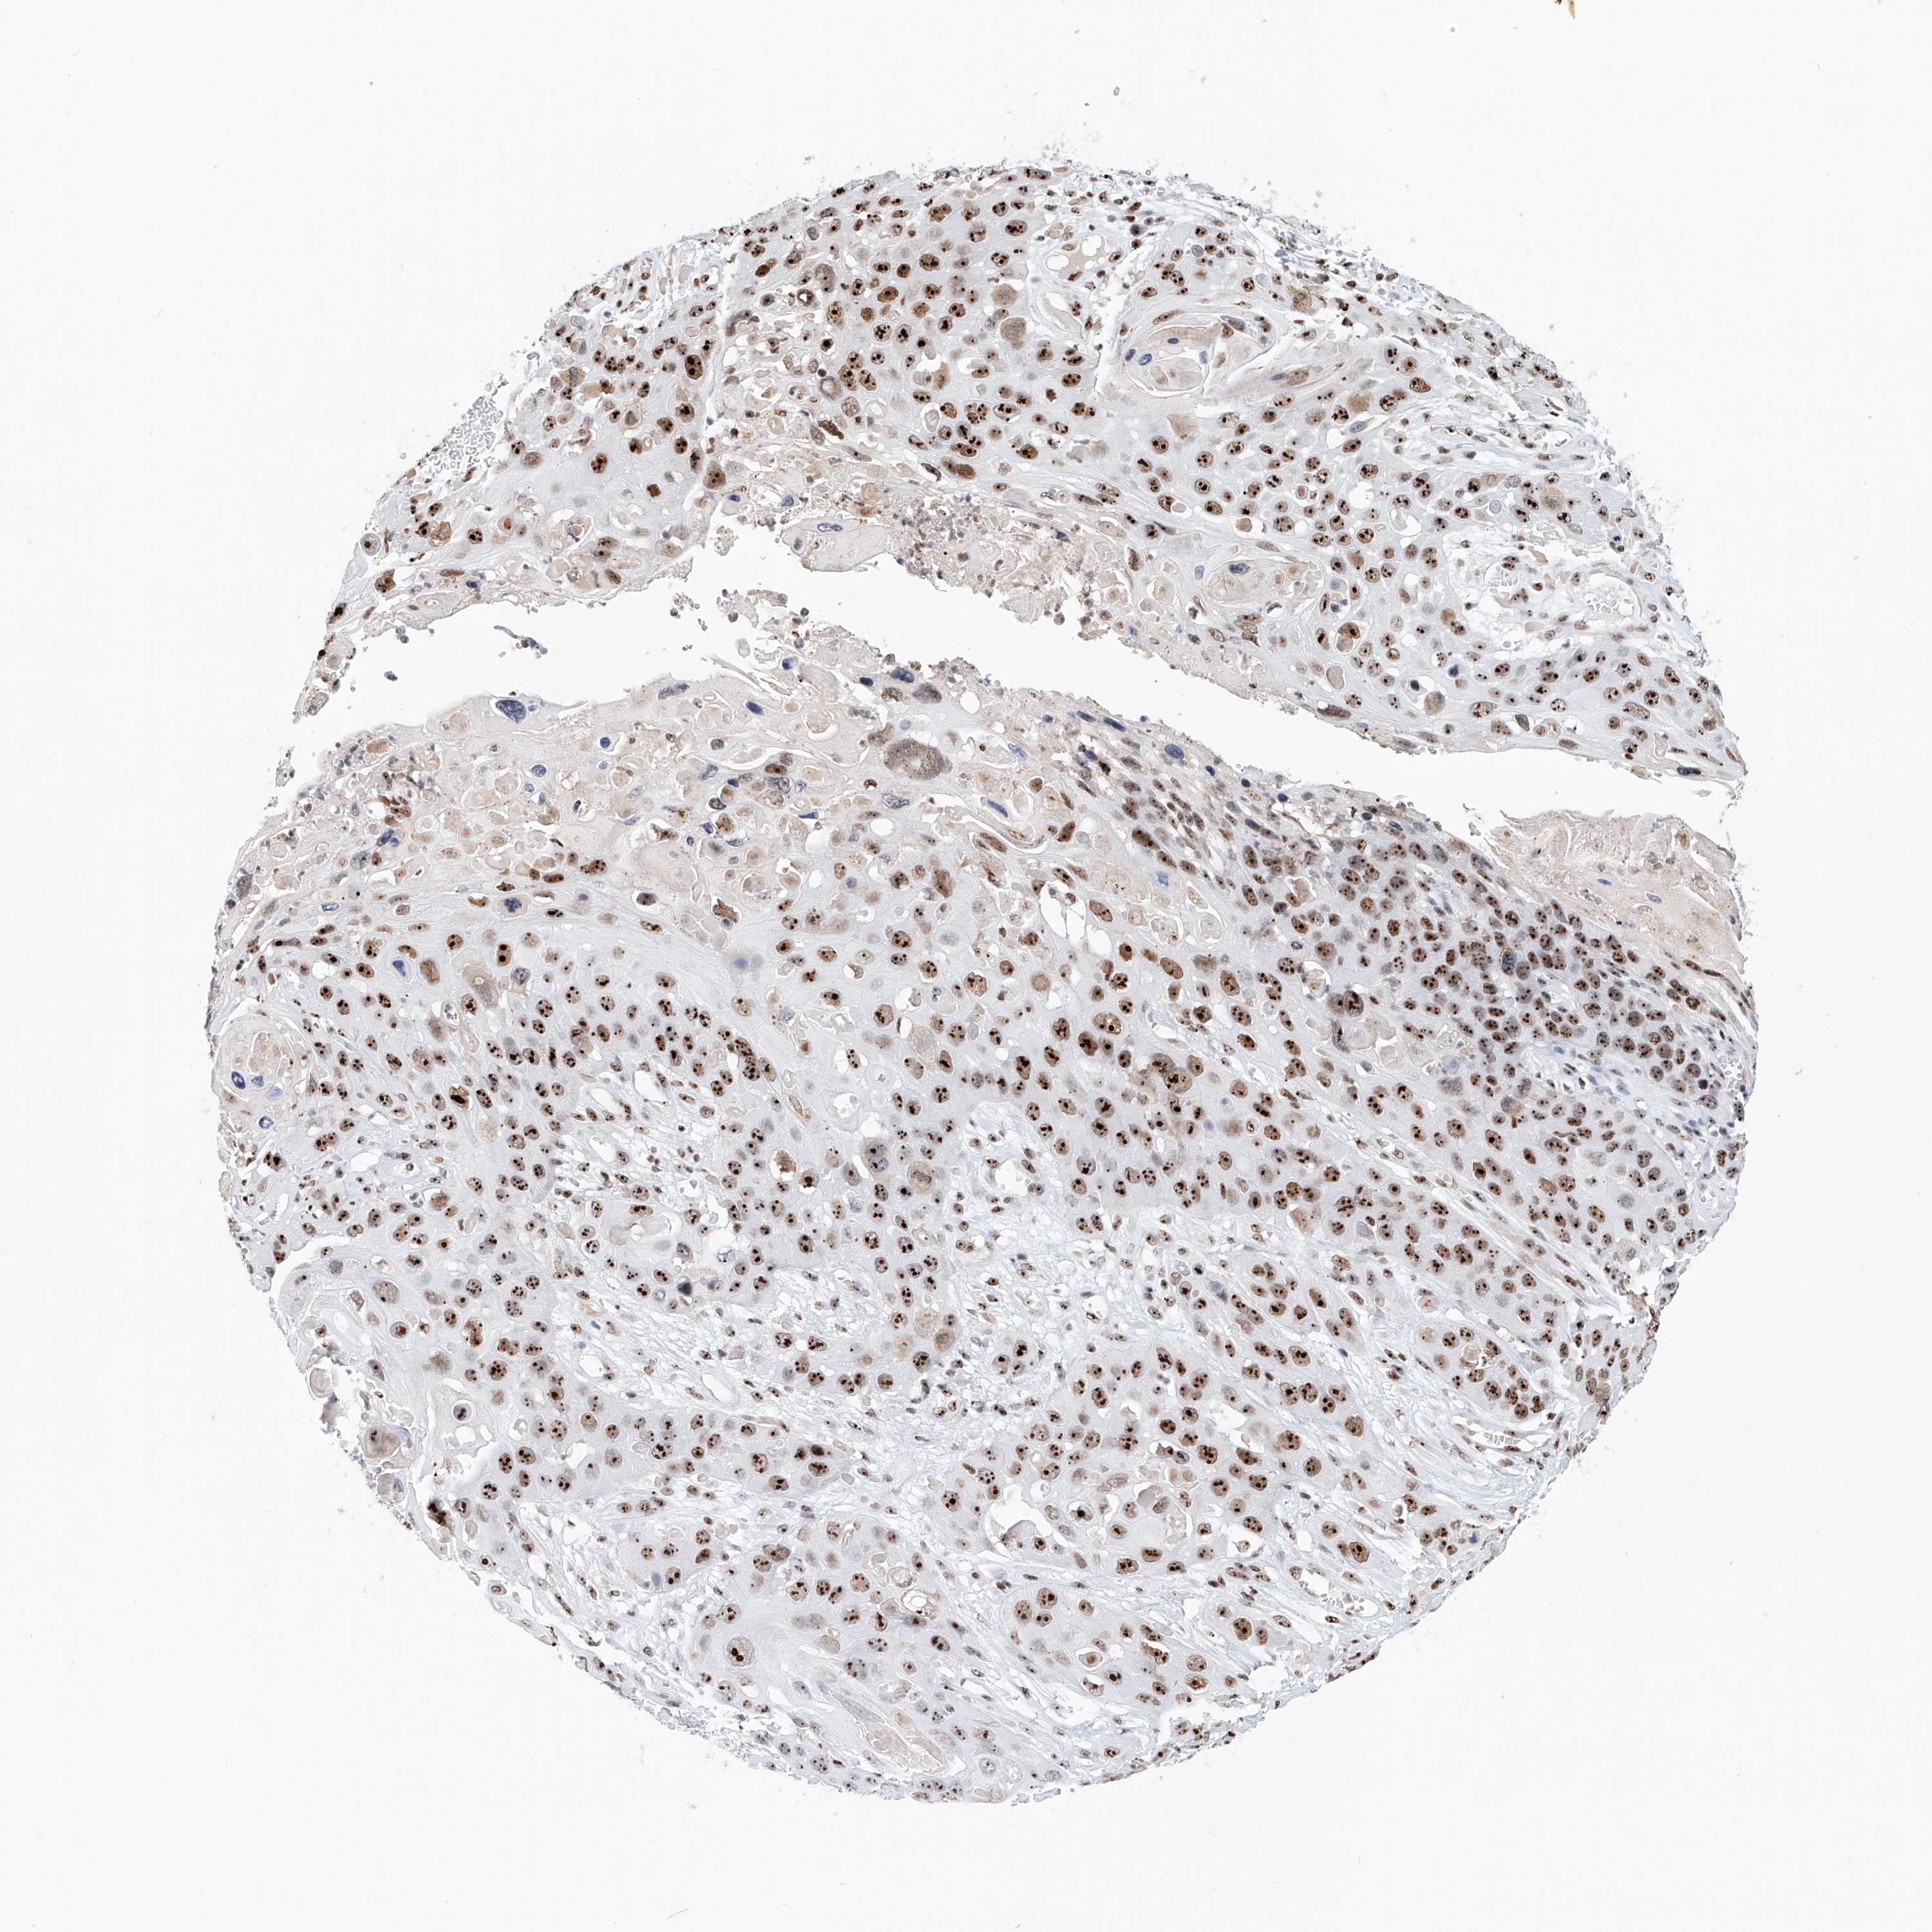

SKIN CANCER - Protein expressioni

A mouse-over function shows sample information and annotation data. Click on an image to view it in a full screen mode. Samples can be filtered based on level of antibody staining by selecting one or several of the following categories: high, medium, low and not detected. The assay and annotation is described here.

Each image is clickable and will lead to virtual microscopy that enables deeper exploration of all samples and also displays staining intensity scores, fraction scores and subcellular localization as well as patient and tissue information for each sample.

Antibody HPA031079

Staining

High

Medium

Low

Not detected

Intensity

Strong

Moderate

Weak

Negative

Quantity

>75%

75%-25%

<25%

None

Location

Nuclear

Cytoplasmic/membranous

Cytoplasmic/membranous,nuclear

Basal cell carcinoma